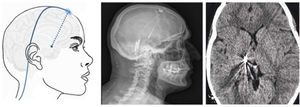

▪Thalamic stimulation. Deep brain stimulation is rarely used in TN, but has been performed in cases secondary to MS or herpes zoster infection and to treat facial deafferentation pain. Other case reports simply refer to untreatable TN. The typical target is the ventral posteromedial nucleus of the thalamus (Fig. 9), the periventricular/periaqueductal grey matter, or both. Pain decreased in 37%–75% of the 15 reported cases, with follow-up times shorter than 30 months.80

TN is diagnosed clinically. Patients consulting due to facial pain (whether paroxysmal or continuous) should be assessed thoroughly (history-taking and physical examination). In the ICHD-3, pain attributed to a lesion or disease of the trigeminal nerve is categorised into TN and painful trigeminal neuropathy. In turn, TN is divided into 3 main types according to pain aetiology: classical, idiopathic, or secondary. The most relevant conclusions of this review are that: